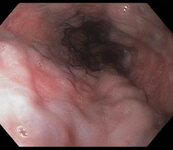

Ulcer in the mid-oesophagus with a visible vessel

From the collection of Douglas G. Adler, MD